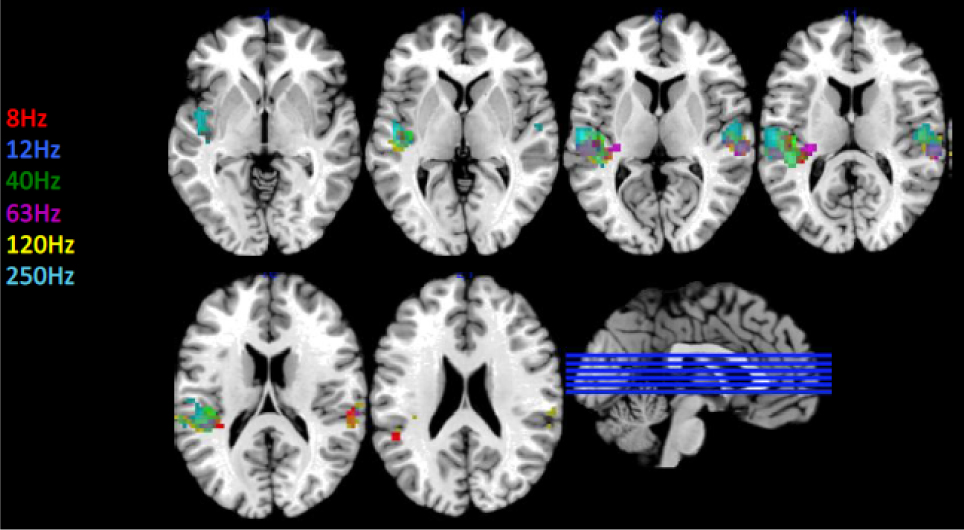

The results show that excitation of the primary auditory cortex is detectable from 8 hertz on, which is an octave less than what has been assumed so far. All the trial persons affirmed that they heard something whereas the observations showed a reaction in certain parts of the brain playing a role in emotions. Different parts of the brain were shown to react to different frequencies of sound. Figure 2 (courtesy Christian Kock, Physikalisch-Technische Bundesanstalt (PTB)) shows the sample activation of auditory cortex during stimulation of the ear by low-frequency sound and infra sound. The figure shows the areas of the brain stimulated by the simple sounds generated at the given frequencies.

Sample activation of auditory cortex during stimulation of the ear by low-frequency sound and infra-sound (courtesy of Christian Kock, Physikalisch-Technische Bundesanstalt (PTB)). The brain activation at stimulus frequencies between 8 Hz and 250 Hz is detected by using fMRI images in various sectional planes through the brain.